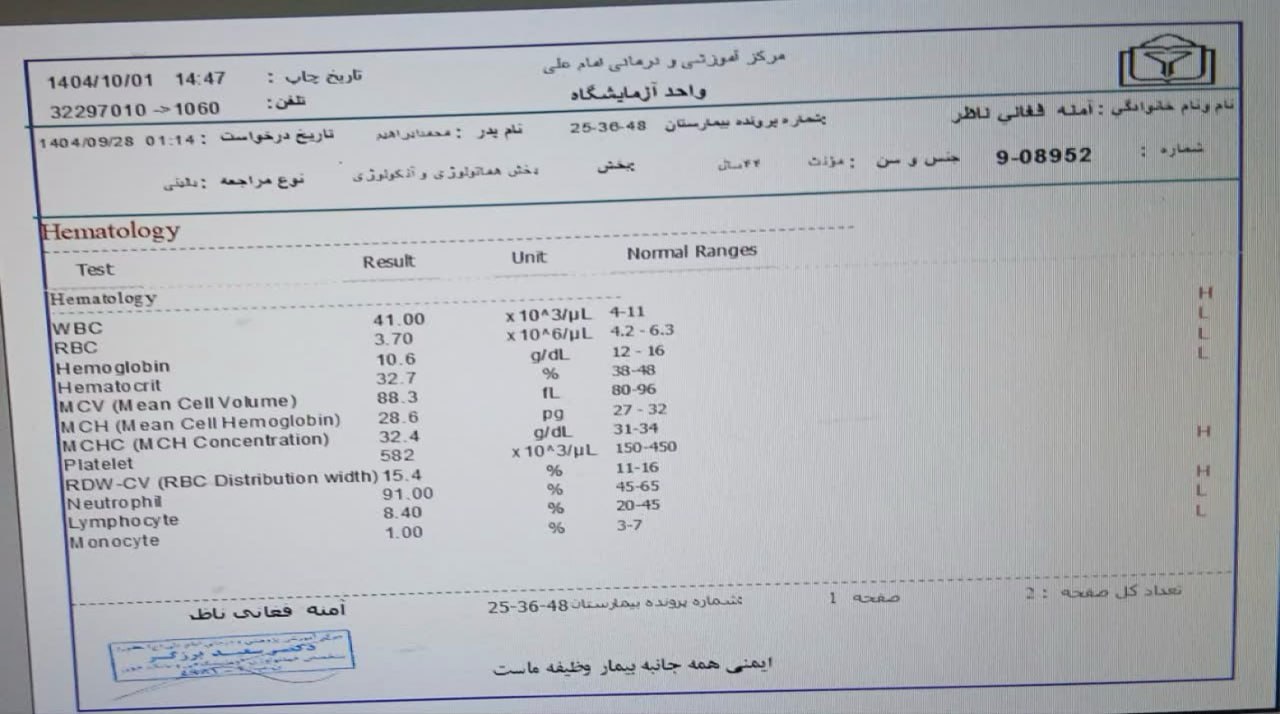

به ترتیب؛ روز ها: ۱۹ آبان, ۲۸ آذر, ۲۹ آذر, ۳۰ آذر

به ترتیب؛ روز ها: ۱۹ آبان, ۲۸ آذر, ۲۹ آذر, ۳۰ آذر

۱۹ آذر

۱۹ آذر

به ترتیب؛ روز ها: ۲۸ آذر, ۲۹ آذر, ۳۰ آذر, ۱ دی

۱ دی